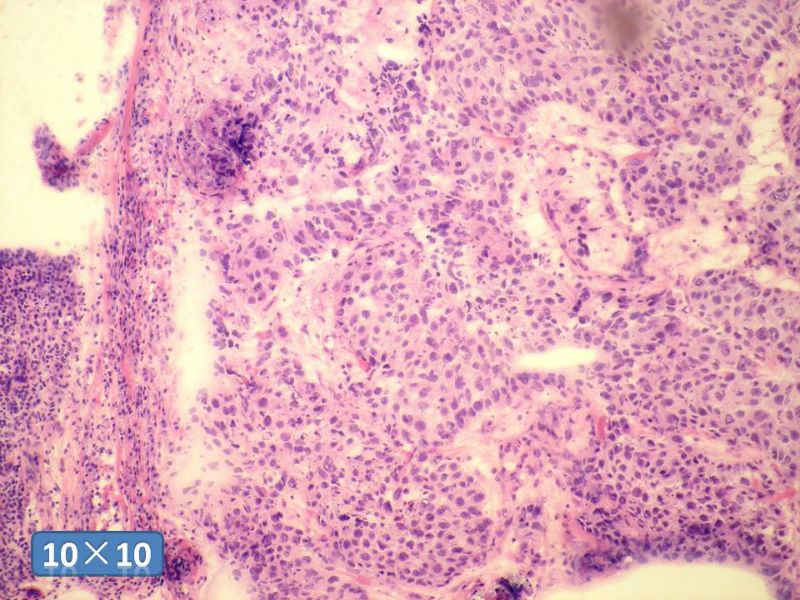

女性,50岁,乳腺肿物,冰冻切片(图1-25)

HE